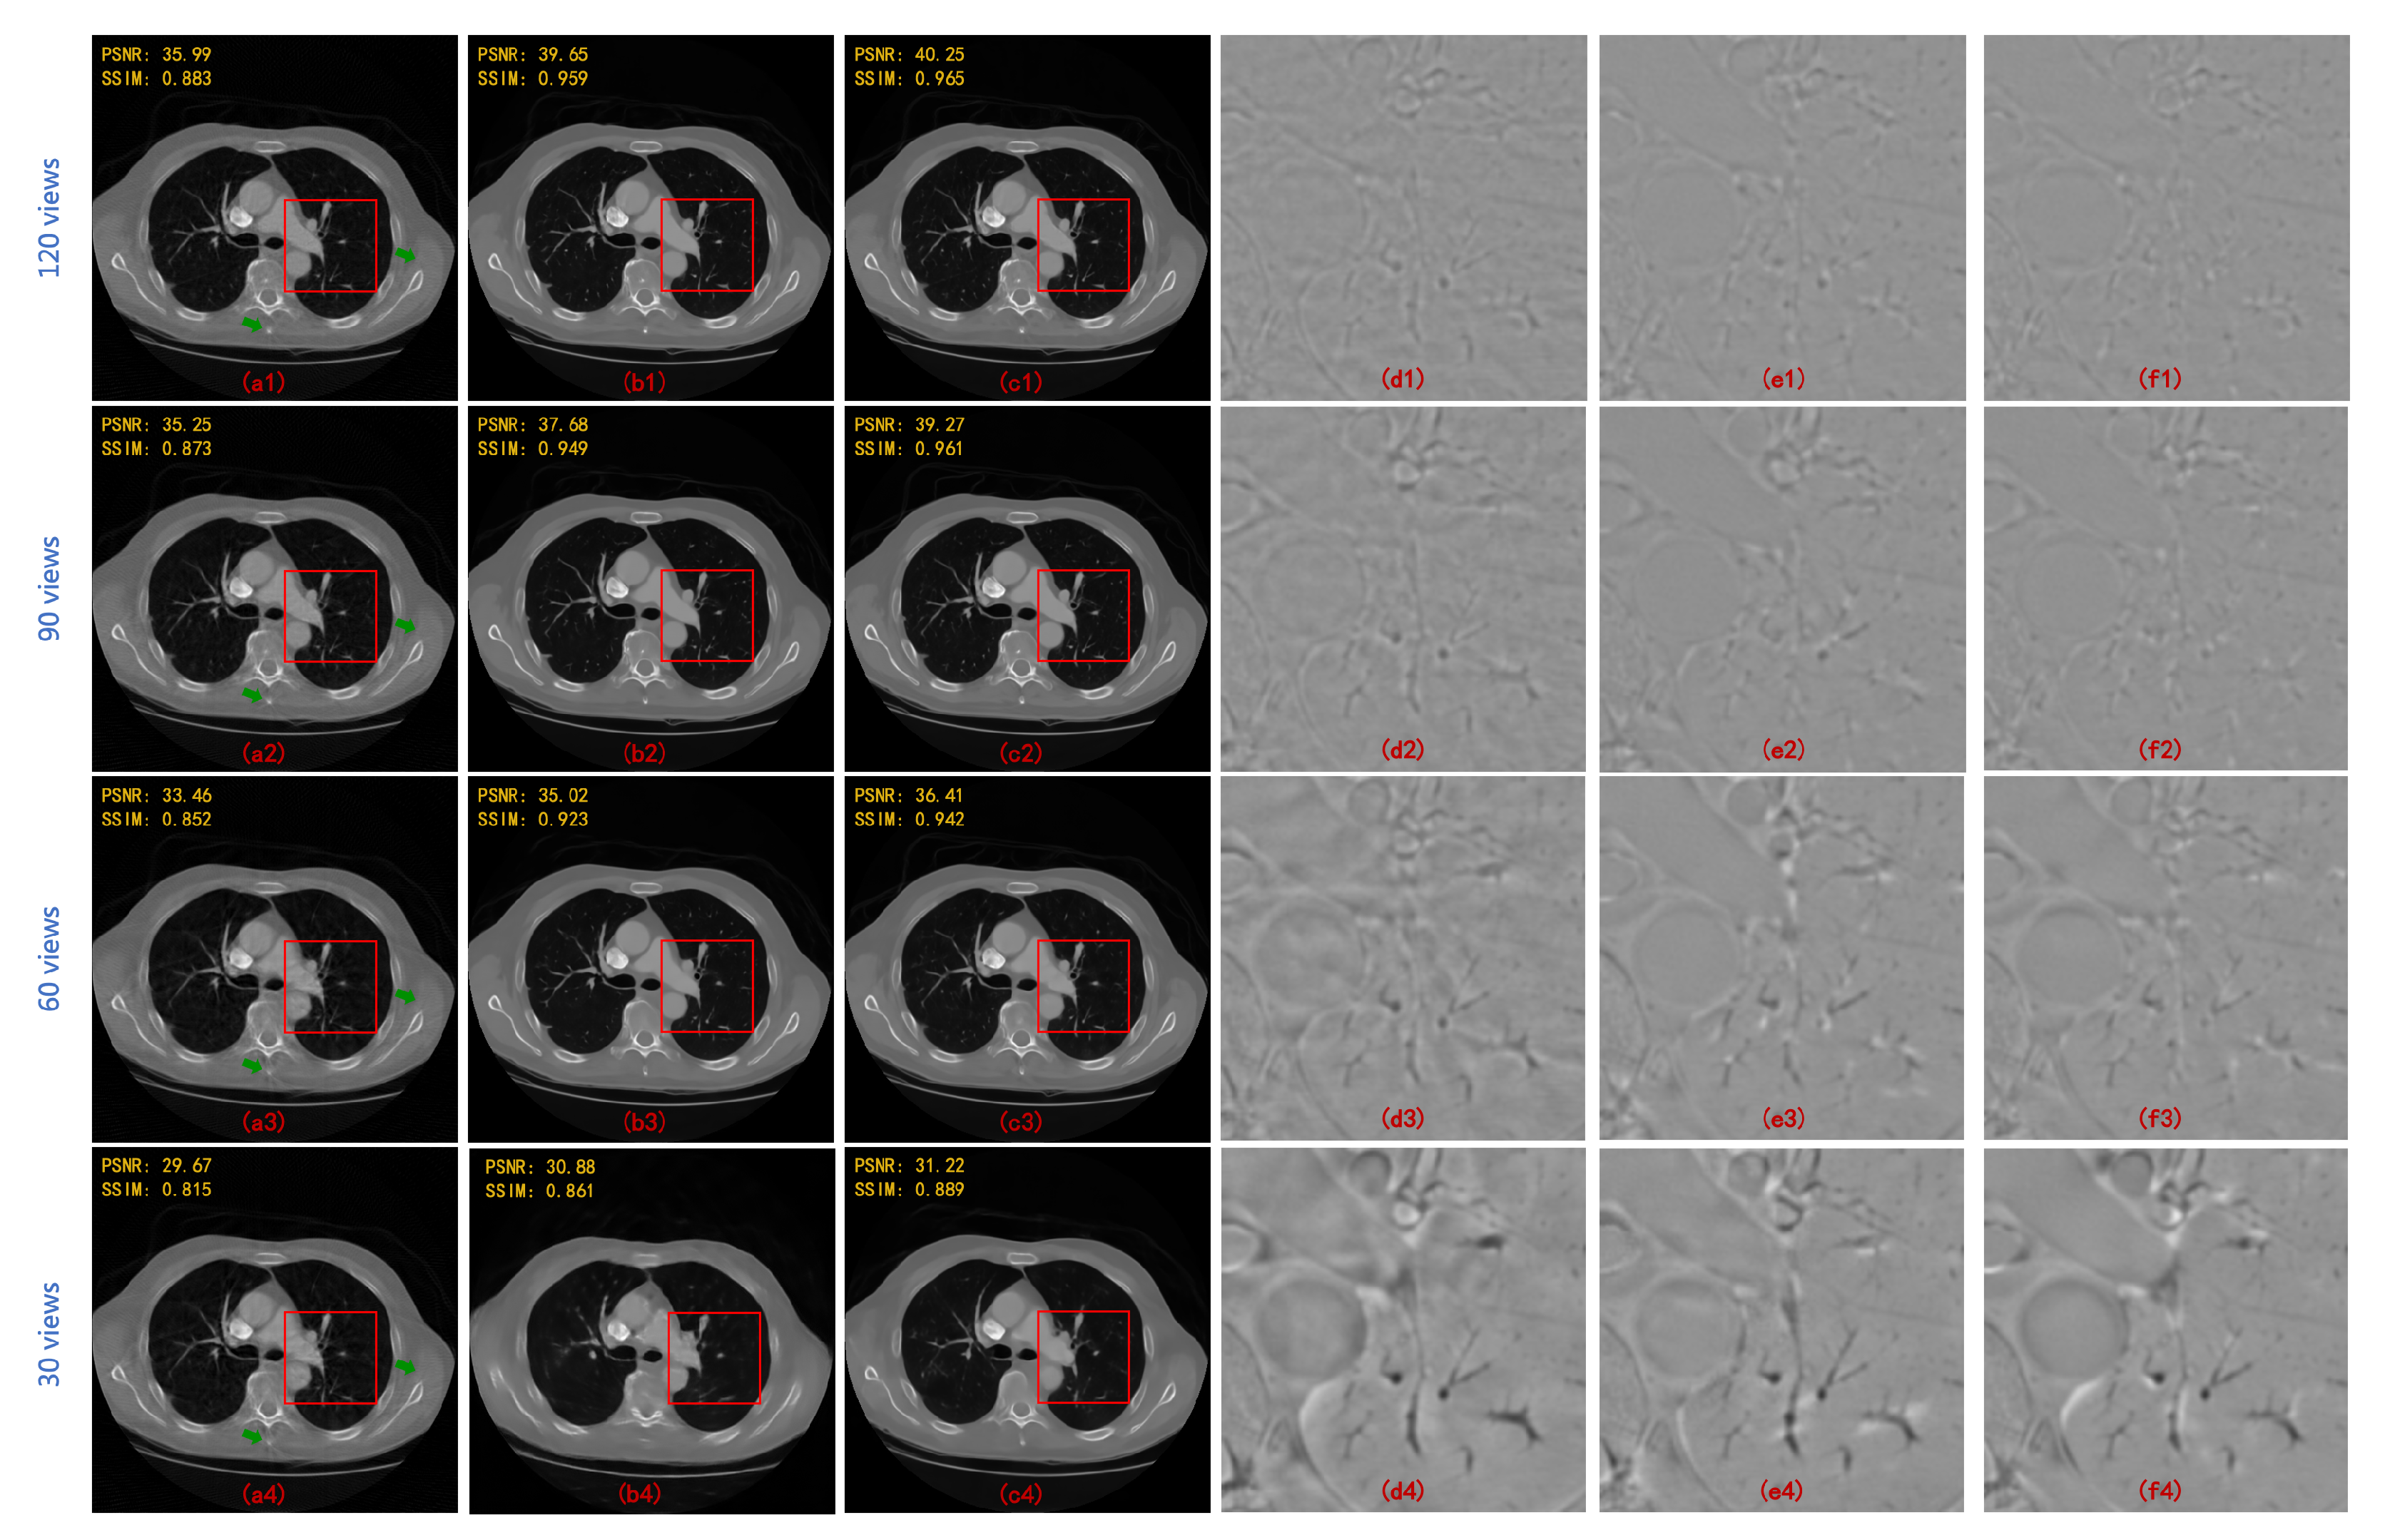

| FBP | Linear + FBP | SART-TV | Proposed | |

|---|---|---|---|---|

| 120 views | 28.725 | 30.241 | 34.405 | 41.049 |

| (3-degree) | 0.558 | 0.802 | 0.903 | 0.958 |

| 90 views | 26.702 | 28.475 | 32.190 | 40.204 |

| (4-degree) | 0.483 | 0.765 | 0.862 | 0.956 |

| 60 views | 23.259 | 26.279 | 30.085 | 37.718 |

| (6-degree) | 0.391 | 0.698 | 0.810 | 0.938 |

| 30 views | 19.496 | 23.399 | 26.711 | 33.100 |

| (12-degree) | 0.280 | 0.624 | 0.726 | 0.891 |

| 90 Views | 60 Views | |||

| PSNR | SSIM | PSNR | SSIM | |

| FBPConvNet [13] | 37.611 | 0.921 | 35.578 | 0.896 |

| RED-CNN [14] | 37.209 | 0.902 | 34.528 | 0.859 |

| DD-Net [22] | 36.380 | 0.912 | 34.424 | 0.892 |

| MWCNN [23] | 38.664 | 0.943 | 36.531 | 0.921 |

| HDNet (WCNN-based) [29] | 34.506 | 0.900 | 32.259 | 0.869 |

| HDNet (Unet-based) [30] | 35.459 | 0.903 | 33.377 | 0.886 |

| HDNet (WUnet-based) | 36.750 | 0.924 | 35.132 | 0.904 |

| HDNet (MWCNN-based) | 40.204 | 0.956 | 37.718 | 0.938 |